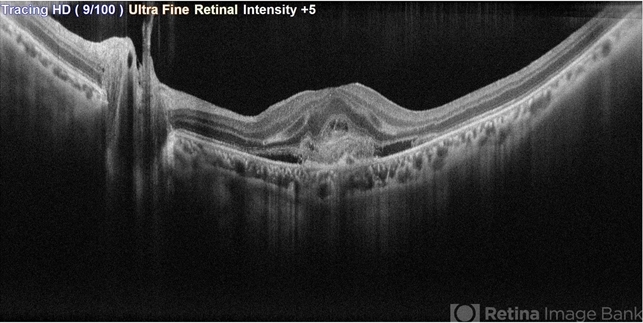

- SRNVM, OCT

Scanning laser ophthalmoscope

Mirante - Description

- OCT image of a 45 year old female with SRNVM in the LE